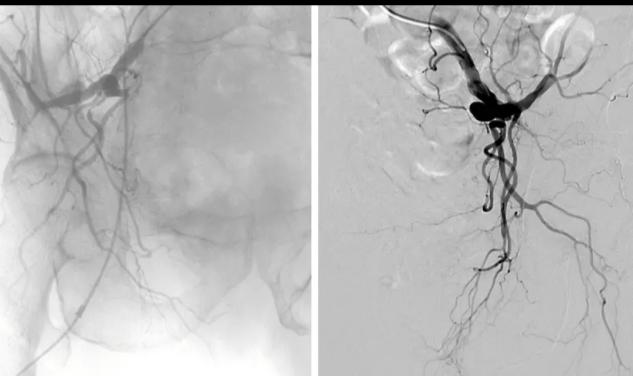

八旬老人血尿不止,微创介入栓塞显奇效

近日,86岁罗爷爷因全程肉眼血尿10+天,在当地卫生院输血治疗数天血尿未得到明显改善,继而出现乏力,面色苍白,精神,食纳不佳等症状,为求进一步诊治遂入住我院泌尿外科。入院后完善CT及膀胱镜检查可明显因前列腺增生并出血,予留置尿管,持续膀胱冲洗,应用止血药等处理均未能很好改善出血。

泌尿外科团队拟手术治疗,却因患者高龄,且合并有频发室性早搏,冠心病,下肢静脉血栓,慢阻肺等严重基础疾病,常规前列腺手术风险很大,家属亦非常顾虑;泌尿外科吴永福主任很快调整治疗方案,建议患者可行前列腺动脉栓塞术止血,同时也可使前列腺萎缩,达到治疗目的,挽救患者生命,改善生活质量。在征得患者家属同意后入院第2天在放射科、介入室、泌尿外科医护人员共同协助下,仅用约1小时时间便为患者成功实施盆腔动脉造影前列腺动脉栓塞术,术后患者安返病房,未诉特殊不适。术后当天血尿较前明显减轻,术后第1天未见新的出血。

泌尿外科吴永福主任介绍:前列腺动脉栓塞治疗是阻断前列腺动脉血液供应,使前列腺增生部分坏死,萎缩,从而缩小前列腺体积。改善排尿困难,出血。主要优点是微创,并发症少,恢复快,甚至可作为门诊手术开展,是缓解前列腺增生患者下尿路症状很有潜力的治疗措施。